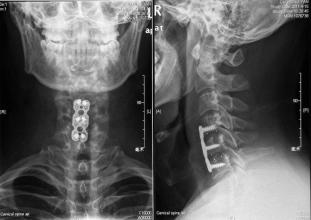

影像學檢查:

(一)頸椎X線攝片:目前最常用的頸椎X線攝片為頸椎側(cè)位片,其次為前后位片、齒狀突開口位片、屈伸動力位片以及左右斜位平片。